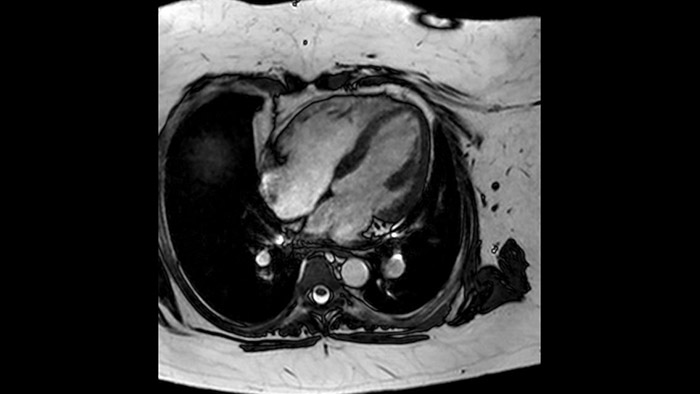

Diagnostic and prognostic utility of cardiac MR is increasing. Assess the anatomy and function of the heart using cine acquisitions, acquire information about perfusion and viability of the cardiac tissue, visualise potential edema with black blood sequence, access and even quantify tissue characterisation with CardiacQuant.

Due to the design of the BlueSeal magnet there is a negligible energy transfer from gradient coil to the magnet. This allows to maintain perfect B0 stability overtime which is especially beneficial for B0 sensitive acquisitions like cardiac bTFE sequences.

Addition of Compressed SENSE to your cardiac exams reduces the time spent in the MRI scanner for the patient and enables the reduction of breath hold times while maintaining virtually equal image quality4. Compressed SENSE is applicable to both 2D and 3D acquisitions.